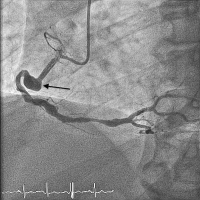

Abbildung 2: Angiographische Darstellung des RCA-Aneurysmas

Keywords:

Aneurysma

,

Angiographie